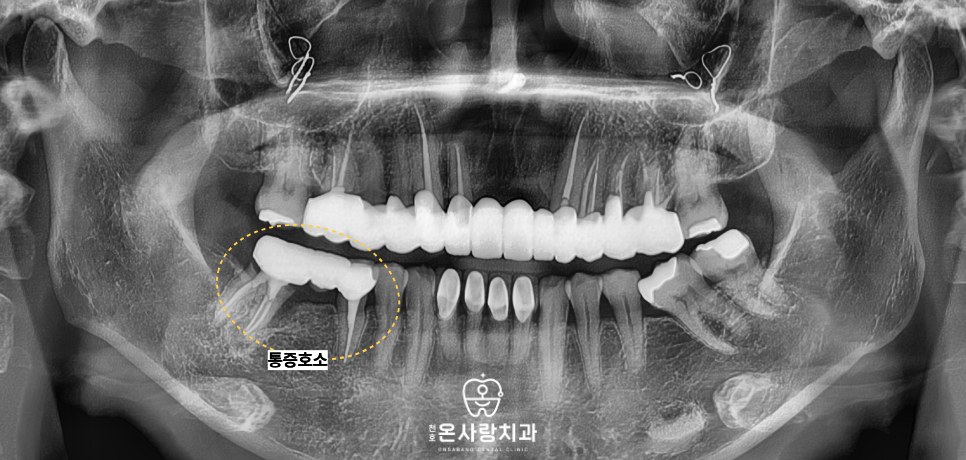

이번에 천호동치과 천호온사랑치과를

찾아주신 환자분께서는

아래턱 오른쪽 끝부분인 47번 어금니 부위의

극심한 통증을 호소하며 내원하셨습니다.

해당 부위는 이미 오래전에

브릿지 치료를 받으셨던 상태였고,

통증의 원인을 정확히 파악하기 위해서는

우선 기존에 연결되어 있던

브릿지 보철물을 제거해야만 했습니다.